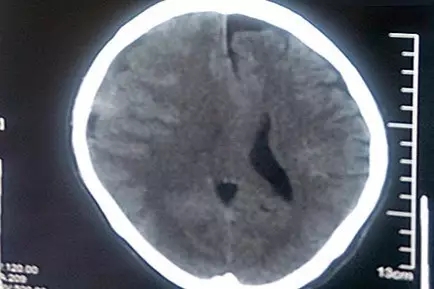

老冯才告诉了家人。县医院CT诊断结果比他想象的严重得多!这大树枝把他砸出了亚急性硬脑膜下血肿,出血量较大,脑中线已经移位,并有脑疝风险。马不停蹄的老冯一家到了省城的三甲医院,接着又赶到了上海的三甲医院,然而都以各种理由被建议转院治疗。不幸中的万幸是,老冯的亚急性硬脑膜下出血相比急性硬脑膜下出血,出血速度稍缓,所以血肿形成至脑受压的过程略长,为老冯四处求医争取了宝贵的时机。

患者术前CT影像:脑中线结构向左偏移